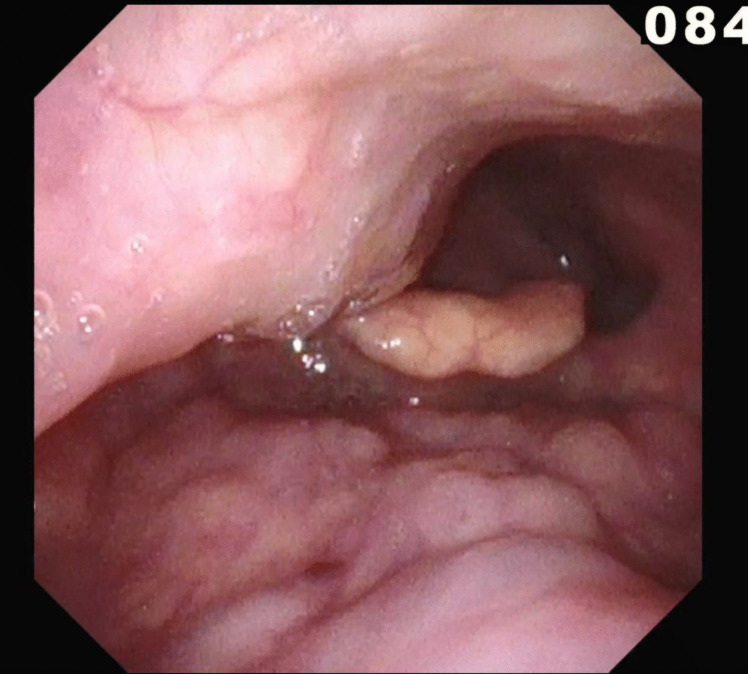

Purpose: We present a case of dysphagia caused by an aberrant internal carotid artery (ICA). By reporting this rare occurrence, we hope to highlight the anomaly as a differential in cases of persistent, progressive dysphagia.

Results: Even though the symptomatic mass effect of the ICA warranted the option of surgical intervention, due to a patient-centered approach with an emphasis on personal preference, the patient was instead referred for specialized ergotherapy.